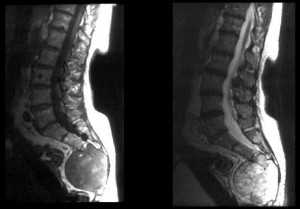

4. МРТ при остеохондроме позвоночника:

• Т1-ВИ:

о Гиперинтенсивность центральной зоны (костного мозга), окруженная гипоинтенсивным кортикальным слоем

о Гипо-/изоинтенсивный хрящевой колпачок, образованный гиалиновым хрящом

• Т2-ВИ:

о Изо- или гипоинтенсивность центральной зоны (костного мозга), окруженная гипоинтенсивным кортикальным слоем

о Гиперинтенсивный хрящевой колпачок, образованный гиалиновым хрящом

• Т1-ВИ с КУ:

о Может отмечаться периферическое усиление и усиление сигнала перегородок в хрящевом колпачке